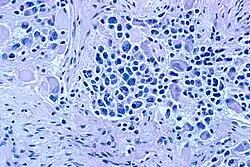

Das Ganglioneuroblastom (früher auch als malignes Ganglioneurom bezeichnet) ist ein seltener Tumor des Nervensystems, dessen Differenzierung zwischen Neuroblastom und Ganglioneurom einzuordnen ist. Nicht-neoplastische Schwann-Zellen und deren Vorläufer Zellen spielen eine entscheidende Rolle im Ausreifungsprozess von Neuroblastomen zu Ganglioneuroblastomen und Ganglioneuromen.[1]

Morphologie und Biologie

Es werden zwei Formen unterschieden: Die schwannzell-stroma reiche (imperfekte) Variante mit allen Stufen einer neuronalen Differenzierung, sowie die Mischform aus schwannzell-stroma reichen und schwannzell-stroma armen Anteilen, bzw. unreife Variante. Letztere Variante hat eine etwas schlechtere klinische Prognose.[2] Im Gegensatz zur früheren Auffassung haben nicht-neoplastischen Schwann-Zellen und deren Vorstufen eine zentrale Rolle im Ausreifungsprozess von Neuroblastomen zu Ganglioneuroblastomen/Ganglioneuromen. Verschiedene Studien konnten nachweisen, dass diese Zellen maßgeblich zur Differenzierung der Tumorzellen beitragen. Diese Untersuchungen stellen eine in der Tumorbiologie außergewöhnliche Konstellation dar: Eine nicht-neoplastische Zellpopulation stimuliert die Differenzierung und den Zelltod von Tumorzellen.[3]